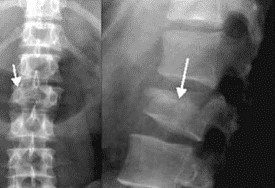

Gãy cổ xương đùi

15/02/2019

Những điều cần biết về gãy cổ xương đùi